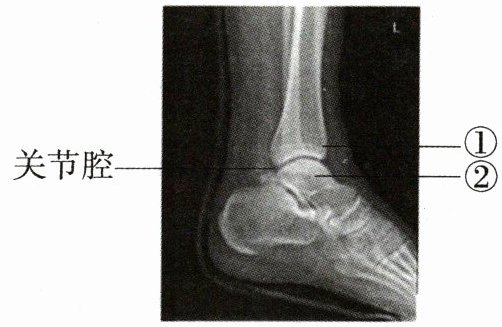

7. 小明在打篮球过程中突然觉得左脚脚踝处剧烈疼痛,经检查得到踝关节射线透视图像,①②表示踝关节内的结构。下列说法错误的是(

A.①②表面覆盖着关节软骨,可缓冲运动时产生的震荡

B.关节腔内有滑液,使关节灵活

C.踝关节在运动中起支点作用

D.由图可知小明疼痛的原因是踝关节脱位

D

)A.①②表面覆盖着关节软骨,可缓冲运动时产生的震荡

答案:

7.D